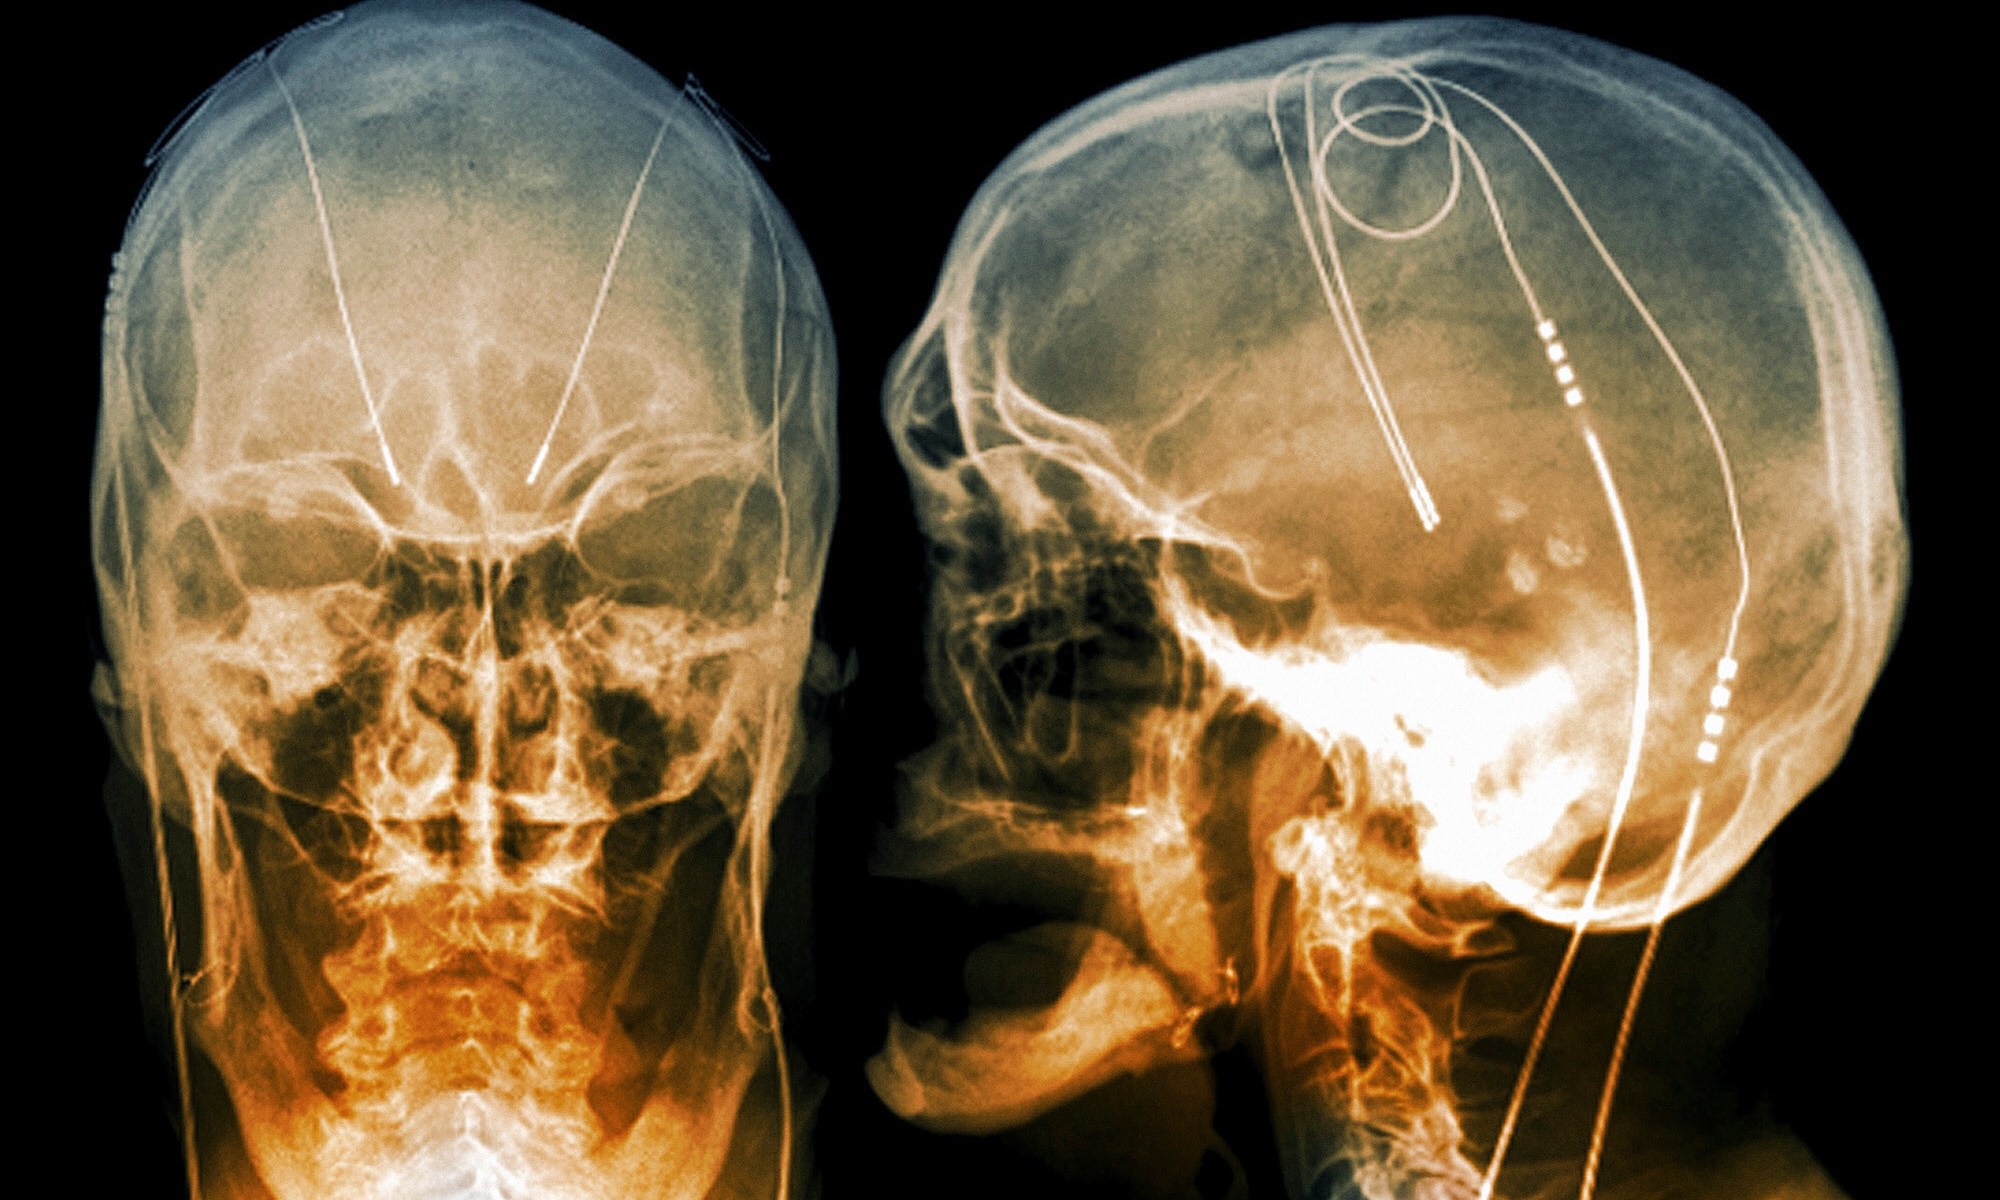

Dr. Collins’s experimental contraption uses “Precision Deep Brain Stimulation”, and uses implanted electrodes to produce electricity which regulates the human brain. The system can “recognize” specific patterns of brainwaves associated with depressive behaviors, and regulate the electric impulses.

Deep Brain Stimulation (DBS) involves the surgical implanting of electrodes into the brain, similar to those used in lab rats. These electrodes are connected via an insulated wire, connecting to a neurostimulator implanted under the skin. The neurostimulator regulates the electronic impulses being sent deep into the brain. This experimental technology has been known to produce life altering side effects, including change in human behavior and total change in personality. The change is not always to the patients liking, and unpredictably dependent upon the patient.

There have been other medical uses for Deep Brain Stimulation (DBS) such as Parkinson’s disease, and obsessive compulsive disorder (OCD), among other ailments. Deep Brain Stimulation is even described on parkinsons.org, stating it was first approved for the disease in 1997. Severe neurological and alarming personality changes have occurred in many of these patients following DBS treatment. In some cases, patients have stated they have become “complete different people”. This change, is not always a positive. Are the long term neurological risks worth the medical benefits?